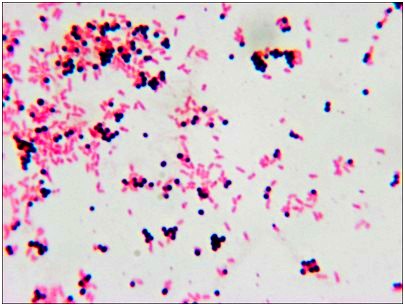

顯微鏡所拍圖片